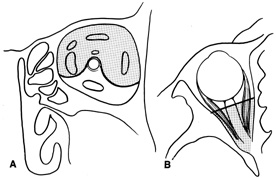

Indications

Transcranial orbitotomy provides access to the superior two-thirds of all the orbital compartments (Fig. 15). In some cases, the craniotomy is used only to provide access to the orbit that is otherwise not possible, such as biopsy of an orbital apex mass. Its primary use is for exploration of tumors involving the orbital apex, or large tumors extending above and medial to the optic nerve. The transcranial orbitotomy also is used as part of combined procedures for approaching tumors involving the orbit as well as the anterior and middle cranial fossae. Most commonly, this involves sphenoid wing meningioma resection.

Fig. 15. Schematic of areas amenable to transcranial orbitotomy. Coronal (A) and axial (B) sections.

The performance of a transcranial orbitotomy requires that the orbital surgeon has a good working relationship with a neurosurgeon interested in diseases of the orbitocranial junction. Often, the surgeons working together on these procedures are part of a larger craniofacial team that uses combined expertise to approach other complicated tumor extirpations and reconstructions of the face and skull base.

The transcranial orbitotomy offers unsurpassed exposure of the superior orbit, orbital apex, and chiasm. Its relatively low morbidity makes this orbitotomy the procedure of choice when safe, wide exposure of the posterosuperior orbit is necessary. It is not indicated for orbital apex lesions lying inferior to the optic nerve, in which an extended lateral orbitotomy and temporal craniotomy may be required.